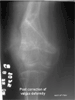

Management (2 stages):

1). Correction of angular deformity and limb length discrepancy by using Ilizarov Method

2). Reduction of patellar dislocation by transfer of tibial tubercle (Fulkerson technique)

At 6 months post last surgery, patient can ambulate independently without any pain in the knee. Patient claims no limitation from activities of daily living. Range of motion of the knee is progressively improving. Presently it is 0 to 100 degrees.